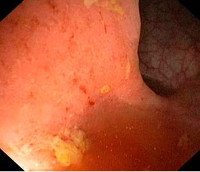

Заболевание диагностируется на основании клинических симптомов, данных пальцевого исследования прямой кишки и дополнительных диагностических процедур. При проведении пальцевого исследования у больных острым проктитом выявляются спазматическое сокращение либо расслабление сфинктера, отечность и инфильтрация слизистой. После извлечения пальца на перчатке обнаруживаются следы крови и слизи. При ректоскопии визуализируются отечность и гиперемия слизистой, эрозии, язвы, кровоизлияния.

При проведении эндоскопии врач осуществляет эндоскопическую биопсию для последующего гистологического исследования материала. Кроме перечисленных исследований, в процессе диагностики острого проктита используют анализы кала на бакпосев и на наличие яиц глистов (для определения причины развития болезни и выбора наиболее эффективной лечебной тактики).